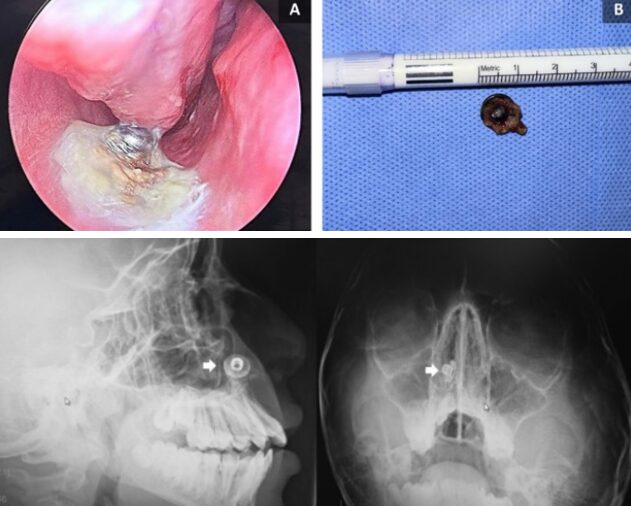

이번 사례를 《국제 외과저널 사례 보고서(International Journal of Surgery Case Reports)》에 보고한 사우디아라비아 애드 디리야 병원 이비인후과 의료진에 따르면, 17세 소년이 치과 검진을 위해 엑스레이 촬영을 받던 중 오른쪽 콧속 비강 바닥에서 이물질이 발견됐다. 소년은 코에 아무것도 넣은 적이 없고, 그때까지 아무런 증상도 없었다고 말했다.

보고서는 “이 물체는 일부분이 점액으로 덮여 있었으며, 딱딱하고 표면이 반짝이는 것으로 보아 금속 물질인 것으로 보였다”며 “방사선 사진을 통해 이물질의 존재와 이와 관련한 경미한 염증이 확인됐지만, 심각한 뼈 손상이나 부비동 관련 증상은 관찰되지 않았다”고 설명했다.

의료진은 기도로의 이탈 위험을 줄이기 위해 반쯤 앉은 자세에서 국소 마취를 한 후 이물질을 제거했다. 직경 1cm 크기의 금속 단추 제거 실시한 검사에서도 심각한 조직 손상은 보이지 않았다. 환자는 안정된 상태로 퇴원했으며, 비강 세척액을 처방 받았다. 2주 후 추적 검사에서도 소년의 상태는 양호한 것으로 보고됐다.